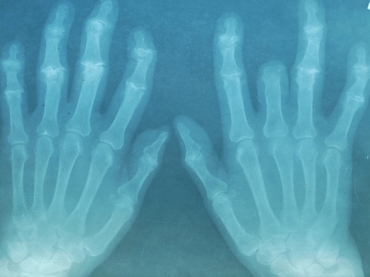

Perguntados sobre quanto haviam bebido no mês anterior à inclusão no estudo, os participantes responderam a questionários detalhados, passaram por exames de raios-x e de sangue e tiveram as articulações analisadas por uma experiente pesquisadora e enfermeira.

"Exames de raios-x mostraram articulações menos danificadas, testes de sangue informaram sobre níveis menores de inflamação e os pacientes que bebem regularmente também reclamaram menos de dores nas juntas, inchaço e deficiência física", diz Maxwell.